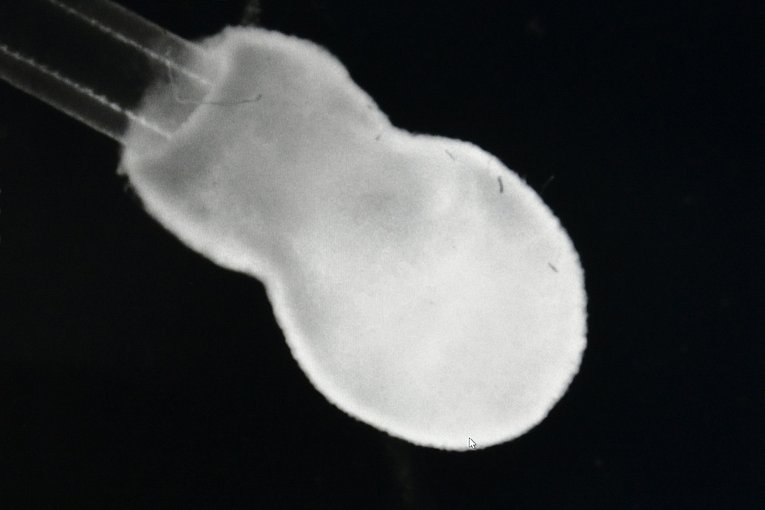

Zur Optimierung des Druckprozesses und der Zusammensetzung der Tinte haben Prof. Engel und Tilman Esser schon einige Hundert Herz muskelringe mit knapp 5 Millimetern Durchmesser gedruckt. Vor Kurzem ist es den beiden sogar gelungen, vereinfachte Modelle eines Herzventrikels, also einer Herzkammer, zu drucken – ballonartige Konstrukte, die etwa 15 mal 8 Millimeter messen und aus je ca. 15 Millionen Zellen bestehen. Der Druckprozess selbst dauert nur wenige Minuten. „Das Besondere an unseren 3-D-gedruckten Ringen und Ventrikeln ist, dass sie nach einigen Tagen tatsächlich schlagen – so wie ein echtes Herz“, betont Felix Engel. „Dazu müssen sich die Zellen zunächst an ihre neue Umgebung gewöhnen und mit den benachbarten Zellen Kontakt aufnehmen. Daraufhin gehen sie einen Verbund ein und das Gewebe beginnt, eigenständig zu kontrahieren.“

Die Herzmuskelringe und -ventrikel untersucht Tilman Esser genau, färbt Zellen ein und macht Gewebeschnitte, um mehr über ihre Zusammensetzung zu erfahren. „Wir wollen außerdem herausfinden, wie viel Flüssigkeitsvolumen die gedruckte Herzkammer pumpen kann und welche Kraft das Gewebe dabei ausübt.“ Für diese Messung werden die Herzmuskelringe über spezielle, leicht elastische „Pfeiler“ gestülpt. „Auch deshalb bot es sich an, die Zellen in Ringform zu drucken“, so Tilman Esser. Der Reifegrad der aktuell gedruckten Zellstrukturen entspricht etwa dem eines Neugeborenen, doch das wollen die beiden Forscher ändern. Prof. Engel: „Wir haben bewiesen, dass es prinzipiell möglich ist, einen lebenden Ventrikel mit dem 3-D-Drucker herzustellen. Nun streben wir an, Ventrikel zu drucken, die mehr Kraft ausüben als die bisherigen, sodass die Pumpleistung des Gewebes mit der eines echten Herzens mithalten kann.“ Doktorand Tilman Esser ergänzt: „Einer unserer nächsten Schritte wäre dann, mit mehreren Biotinten – also mit verschiedenen Druckerkartuschen – parallel zu drucken. Damit könnten wir die Anatomie und den Aufbau eines natürlichen Herzens besser nachempfinden.“ Der Hintergrund: Nur etwa 30 Prozent unseres Herzens bestehen aus Muskelzellen, die übrigen 70 Prozent machen z. B. Blutgefäß- oder Bindegewebszellen aus. Ein so komplexes Organ wie das Herz mittels 3-D-Druck herzustellen, wäre eine echte Bereicherung für die Medizin: „Diese herzähnlichen Systeme könnten wir dann beispielsweise dazu verwenden, die Wirkung von Medikamenten effizienter zu testen als im Tierversuch“, so Felix Engel. „Kleinere Teile des menschlichen Herzens könnten aber auch schon früher durch gezüchtetes Gewebe unterstützt oder ersetzt werden. Das wäre dann eine Art ‚Herzpflaster‘, das zum Beispiel Patientinnen und Patienten mit schwerer Herzinsuffizienz gute Dienste leisten könnte.“